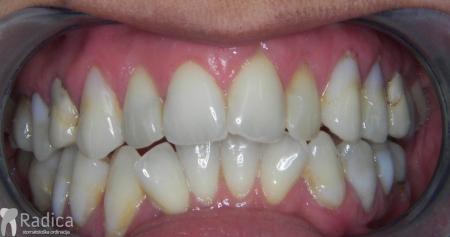

U sljedećem primjeru prikazan je pacijent s kompresijom koji je već bio u ortodontskoj terapiji. Za rješavanje kompresije donje čeljusti izvađen je sjekutić. Nkon terapije je došlo i do smanjenja recesija na očnjacima jer smo pomakli zubni korijen u bolji položaj.